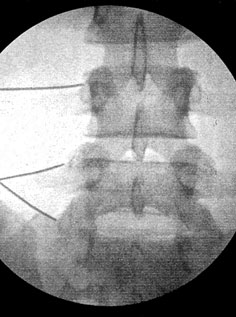

O bloqueio do ramo medial foi realizado através da inserção de uma agulha de 25 gauges e 90 mm pela pele dos pacientes com auxílio de radioscopia até a topografia do ramo medial nos níveis L2, L3, L4 e L5 bilateralmente (Cohen e Raja, 2007). Foi utilizado 0,5ml de lidocaína a 2% sem vaso constritor em cada nível e o controle foi realizado através da mesma técnica acima porém, com a injeção de um ml de água destilada (Cohen e Raja, 2007).

Os pacientes foram colocados em decúbito ventral, monitorizados, porém sem nenhum tipo de sedação (Cohen e Raja, 2007). Foi solicitado aos pacientes que mostrassem em uma régua da escala visual analógica onde sua dor se localizava dentro desta escala e o valor era anotado. Inicialmente foram realizados bloqueios controle com água destilada nos locais onde os pacientes referiam maior sensibilidade a dor. Nos casos em que houve melhora da dor maior que 50% mensurada através da escala visual analógica após 10 minutos com estes bloqueios estes pacientes foram excluídos do protocolo. Nos pacientes em que não houve melhora da dor foram realizados então os bloqueios do ramo medial em todos os níveis citados acima (Figura 3). Após cerca de 10 minutos foi novamente solicitado aos pacientes que mostrassem sua dor na escala visual analógica, nos casos em que a dor melhorou menos que 50% os pacientes foram excluídos do estudo sendo solicitado para eles uma ressonância magnética da coluna lombar para posterior investigação ambulatorial, já nos casos em que a dor melhorou mais de 50% os pacientes foram acompanhados no ambulatório como um potencial caso.

Figura 3. Radioscopia em AP com as agulhas posicionadas na topografia dos ramos medianos de L3, L4 e L5 a esquerda para bloqueio.